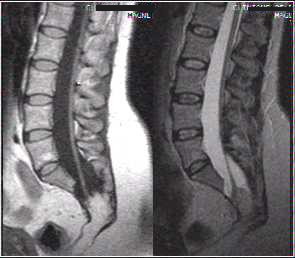

Spine cases